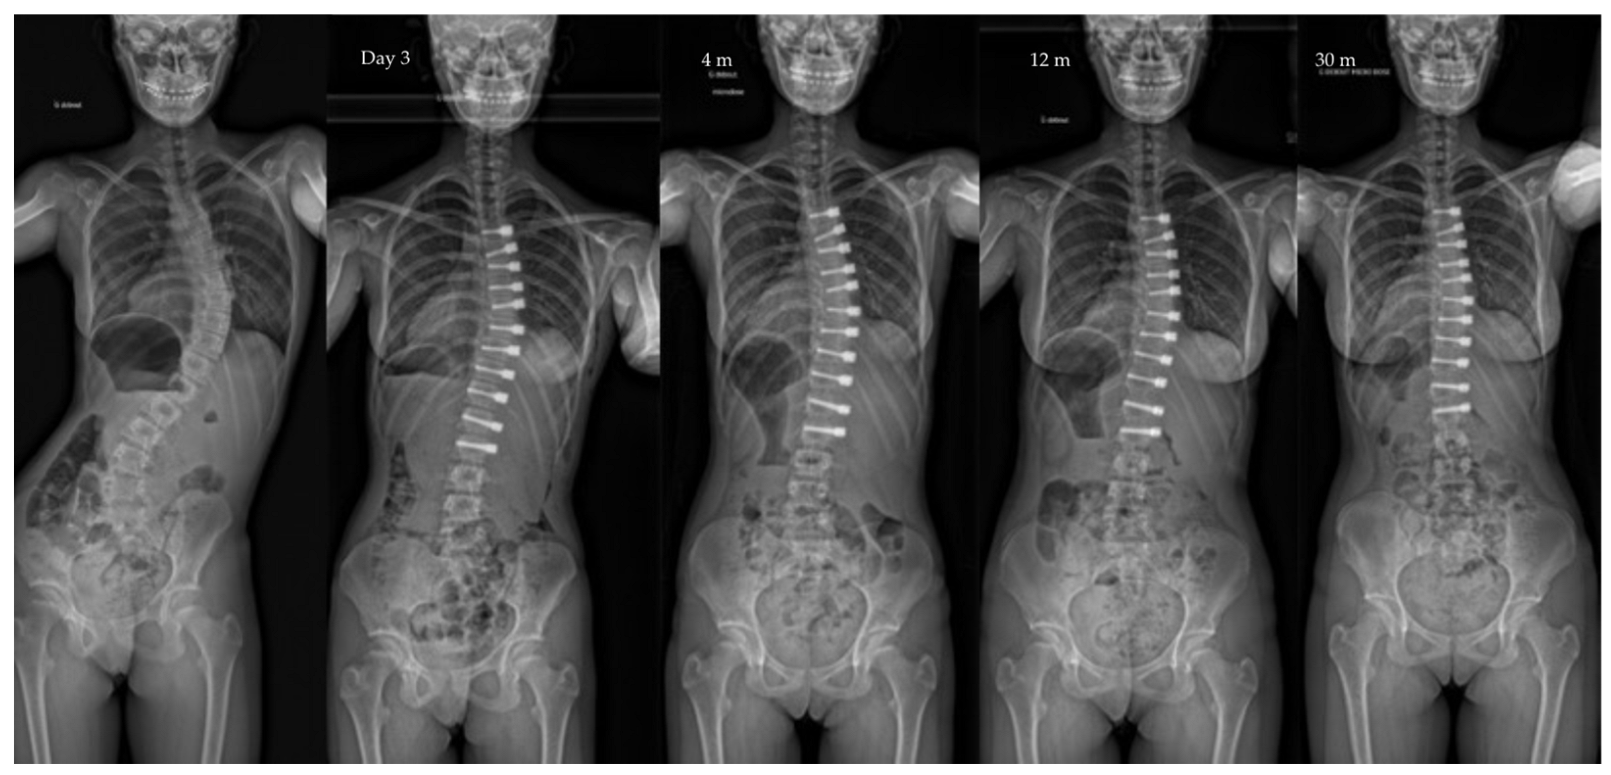

| Pre-op | Post-op Day 3 | Post-op 1y | Last f/u | p-Value | |

|---|---|---|---|---|---|

| Major curve | 49°(8,9°) | 27°(12°) | 22°(12°) | 19°(14°) | <0.01 |

| Secondary curve | 27°(14°) | 23°(15°) | 22°(11°) | 17°(10°) | <0.01 |

| Instrumented curve | NA | 26°(11°) | 23°(10°) | 20°(14°) | <0.01 |

| Kyphosis (T1–T12) | 20°(13°) | 23°(13°) | 25°(12°) | 24°(14°) | 0.06 |

| Lordosis (L1–L5) | 36°(12°) | 32°(13°) | 40°(7°) | 40°(8°) | 0.07 |